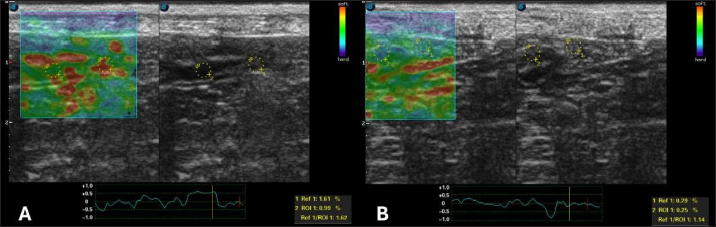

After 30 days of treatment, there were no more laboratory changes (Table 2), the CCECAI was reduced to four (Table 1), and the patient no longer had diarrhea and gained weight. In addition, hyperechogenicity of the intestinal mucosa was reduced, and the values for elastography of the duodenum were as follows: ROI 1 1.61 % and ROI 0.99 %, with an SR of 1.62 (Fig. 5A). In the jejunum, ROI 1 measured 0.29 %, ROI 0.25%, and SR 1.14 (Fig. 5B).

Fig. 5. Semiquantitative elastography of deformation in a cross-section of the intestines of a dog with intestinal lymphangiectasia after 30 days of treatment. The deformation ratio (SR) was obtained by evaluating ROI 1 of the mesentery and ROI 2 of the dorsal portion of the intestinal segment. A duodenum with an SR of 1.62 B-Jejunum with SR=1.14.